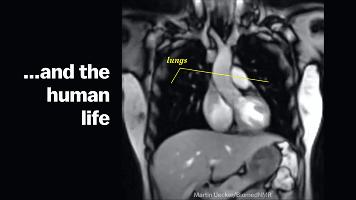

用核磁成像拍攝性行爲過程

威利布羅德·魏吉瑪·舒爾茨(Willibrord Weijmar,爲方便閱讀,後面簡稱“舒爾茨”)一直很好奇,人類在進行性行爲時,身體到底有什麼變化?當雙方達到愉悅值最高點時,身體又會產生怎樣的奇妙反應?

舒爾茨和他的團隊通過當地的媒體招募到了8對志願者夫妻,請他們在覈磁成像設備中進行性行爲,再通過核磁成像觀察志願者在整個過程中的生理反應,包括雙方私密處細微變化。

結果還真讓舒爾茨團隊觀察到了詳細變化:

在親密行爲尤其是達到興奮狀態時,人體會心率加快、呼吸頻率加快、血壓上升,同時耗氧量極速增加(還是個有氧運動),女性的子宮沒有太大的變化,而男性的生殖器會在過程中呈現120°的迴旋鏢形狀。

【核磁成像結果】

志願者在整個過程中做出了相當大的貢獻,因爲在拍攝前,男性被要求喫藥,在過程中,舒爾茨和團隊工作人員也會隨時叫停,以便極其拍攝出更清晰的照片。

1999年,舒爾茨將相關的研究結論發表在醫學頂刊《英國醫學雜誌》上,又在2000年獲得了搞笑諾貝爾獎,但他對性的研究以及使用核磁成像研究的方法,都帶給了人類許多思考。